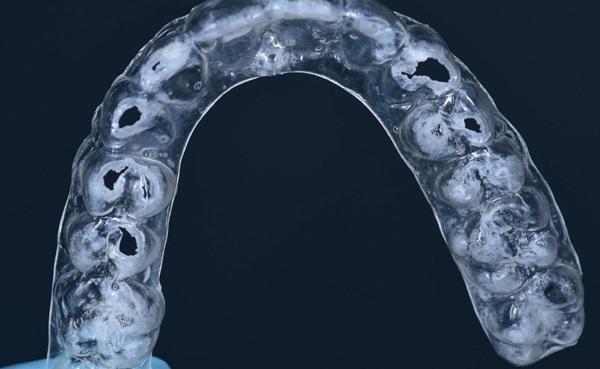

Toekomstige AI-ondersteunde software zal vermoedelijk nog beter risico’s voorspellen op basis van slijtagepatronen, speekselanalyse en leefstijlfactoren. Echter, wanneer er geen scanner in de praktijk beschikbaar is dan is een handige tool het vragen of iemand elke periodieke afspraak zijn retainer meeneemt ter controle. Ontstaan daar slijtfacetten in dan weet je dat iemand s nachts actief is en zul je over moeten gaan op een night guard zoals in het voorbeeld van afbeelding 7-10). Wanneer verwijs je door?